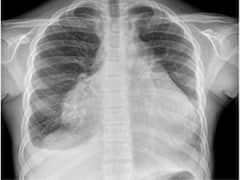

पेरिकार्डियल इफ्यूजन म्हणजे काय?; लक्षणे, कारणे आणि उपचार